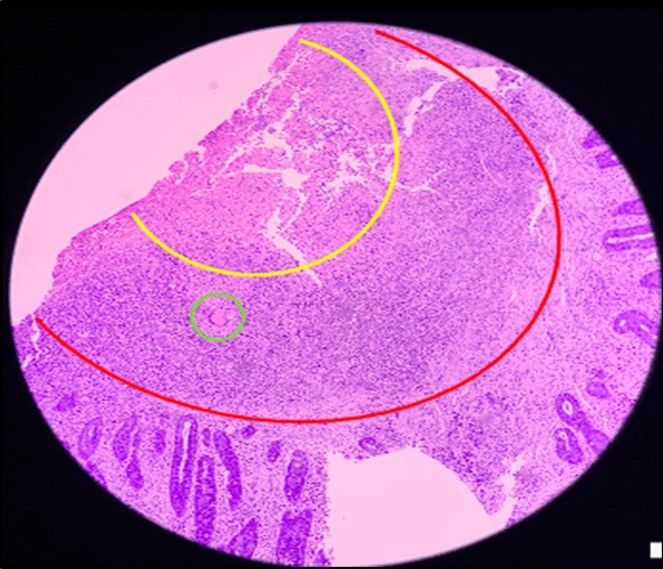

Figure 6.Pathologic slide in the low power field. The area inside the yellow circle is the area of central necrosis. The portion inside the red circle is the peripheral lymphocytic ring, and inside the green circle is the Langhan’s type multinucleated giant cells

Pathologic slide in the low power field. The area inside the yellow circle is the area of central necrosis. The portion inside the red circle is the peripheral lymphocytic ring, and inside the green circle is the Langhan’s type multinucleated giant cells